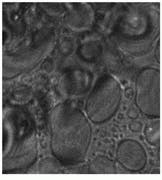

Samples were imaged containing Dacron that had migrated through the breast tissue, forming local aggregates and microstructures (see Fig. 3 and cover). Conventional optical microscopy could not unequivocally determine which of the observed structures were due to Dacron inclusions. One image in Fig. 3 is a bright-field image of the breast-tissue cross section. The other, a Raman image, was taken at 1615 cm-1, which is specific to Dacron. The presence of Dacron was confirmed by using the Raman microscope to take Raman microspectra of these structures at each of the several thousand pixels contained in the chemical image data set.

FIGURE 3. In Raman pathology studies of Dacron in human breast tissue, bright-field image taken through a microscope reveals aggregates (A), while Raman image (taken at 1615 cm-1 ) shows inclusions as bright structures (B).